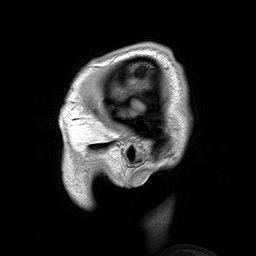

의학 영상 물리학은 진단 및 중재적 방사선 물리학이라고도 한다.[19] 임상 물리학자들은 X-선, 투시법, 유방 조영술, 혈관 조영술, 컴퓨터 단층 촬영과 같은 진단 방사선 물리학 분야의 검사, 최적화 및 품질 보증을 수행한다. 또한 초음파, MRI와 같은 비이온화 방사선 방식과 관련하여 업무를 수행하며, 선량 측정(직원 및 환자)과 같은 방사선 방호 문제와 관련될 수 있다. 많은 영상 물리학자들은 단일 광자 방출 컴퓨터 단층 촬영(SPECT) 및 양전자 방출 단층 촬영(PET)을 포함한 핵의학 시스템과 관련된 경우가 많다.[19]때로는 임상 분야에 참여할 수 있지만, 연구 및 교육 목적으로 특정 혈관 객체를 영상화하는 가능한 방법으로서 혈관 내 초음파를 정량화하는 것과 같은 일을 하기도 한다.[20]

핵의학은 방사선을 사용하여 특정 장기의 기능을 파악하거나 질병을 치료하는 의학의 한 분야이다. 갑상선, 뼈, 심장, 간 및 다른 많은 장기를 쉽게 영상화할 수 있으며, 이들의 기능 장애를 밝혀낼 수 있다. 어떤 경우에는 방사선원을 사용하여 질병이 있는 장기나 종양을 치료할 수 있다. 5명의 노벨상 수상자가 의학에서 방사성 추적자 사용과 밀접한 관련이 있다.전 세계 10,000개 이상의 병원에서 의학에 방사성 동위원소를 사용하며, 절차의 약 90%가 진단을 위한 것이다. 진단에 가장 흔히 사용되는 방사성 동위원소는 테크네튬-99m이며, 연간 약 3,000만 건의 시술이 이루어져 전 세계 핵의학 시술의 80%를 차지한다.[24]